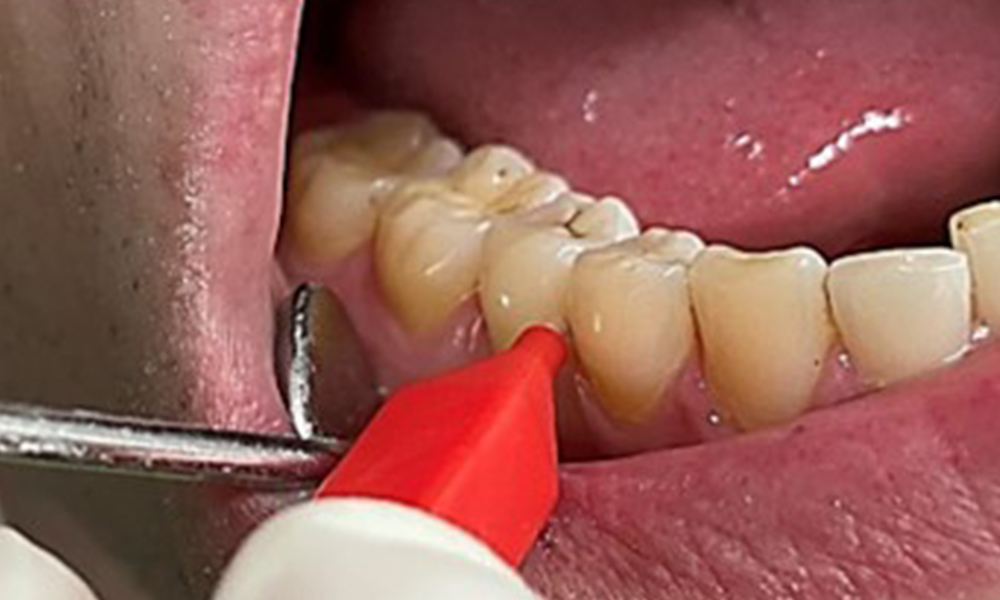

Due to the otherwise favourable general medical condition, the needs determined during the intraoral examination will be decisive for their treatment. It will be essential to periodically determine the probing depths. Gingival bleeding decreases in smokers, which is why the clinical diagnosis of periodontitis can only be made by probing (Fig. 7). Placing exclusive focus on the determination of bleeding indices may obscure existing periodontitis or gingivitis. (5)

Instruction and motivation are important components of these appointments. Good home-based intraoral hygiene behaviour and understanding are important for patients. Plaque accumulation is particularly evident in the cervical regions (Fig. 8).